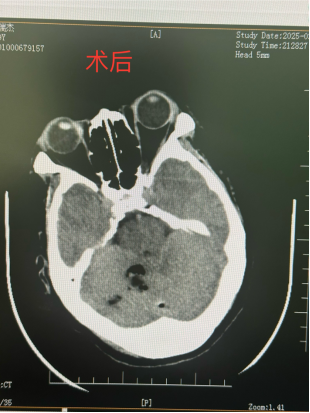

近日,我院接诊到一位因走路时不慎摔伤头部的患者,急诊科医护人员通知家属后立即开通绿色通道陪同患者完善CT检查,我院创伤医疗团队同时至CT室等待。徐学敏科主任明确目前诊断为创伤性小脑血肿,目前患者病情危重需急诊行神经内镜下颅内血肿清除术,完善术前准备后,立即送入手术室。

手术时间约2小时,术后患者恢复顺利,生命体征平稳,术后复查颅脑CT,小脑区域血肿已基本全部清除。